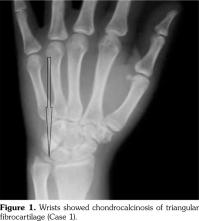

His hand X-rays showed hook like projections arising from radial aspect of second and third metacarpal heads with scapholunate advanced collapse and indentation of distal radius by the scaphoid bone. It also showed CC of the triangular fibrocartilage (Figure 6).